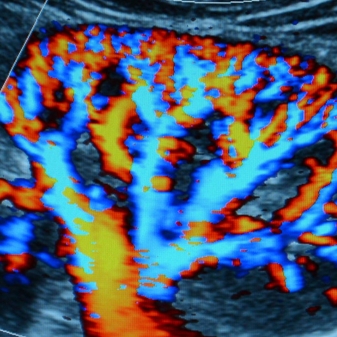

Doppler colorido

Ultrassom que mapeia o fluxo sanguíneo em cores, avaliando direção e velocidade do sangue em artérias e veias para diagnóstico vascular preciso.